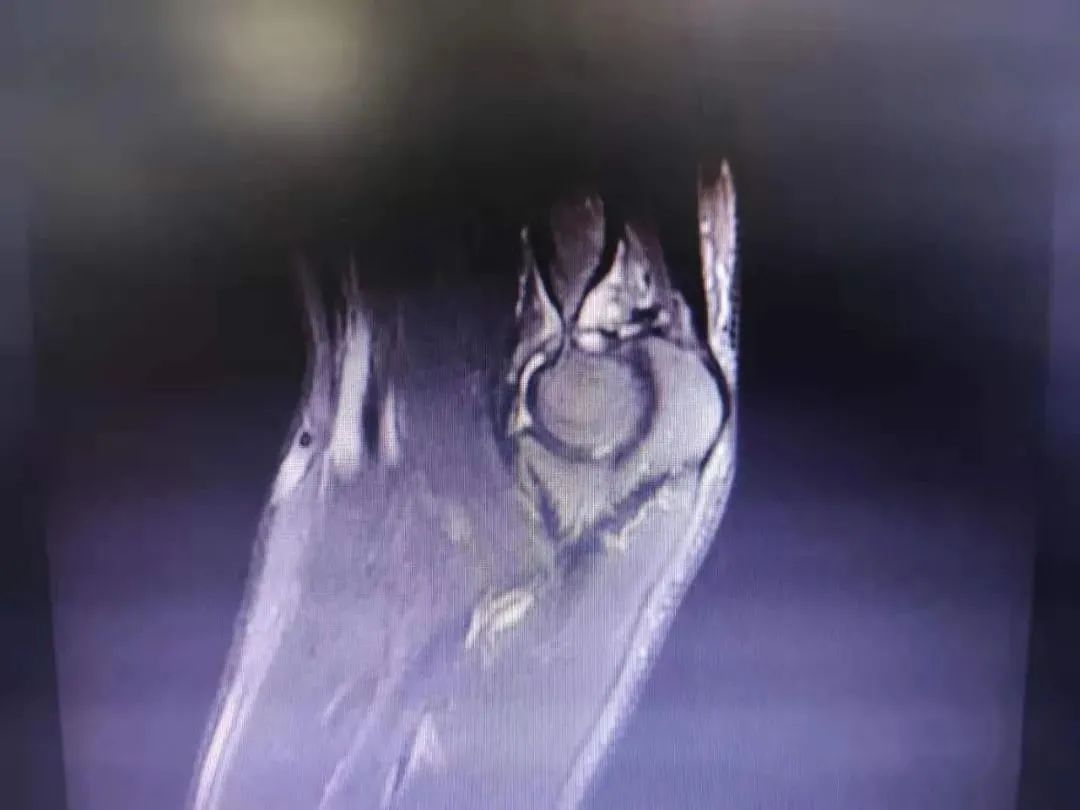

入院后MRI检查(提示肘关节容积变小)